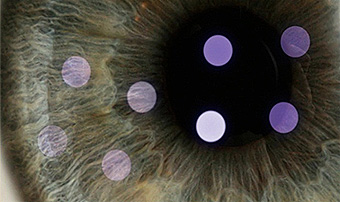

Preoperative Patients wearing soft contact lenses typically are instructed to stop wearing them approximately 6 to 7 days before surgery. One industry body recommends that patients wearing hard contact lenses should stop wearing them for a minimum of three weeks. Before the surgery, the patient’s corneas are examined with a pachymeter to determine their thickness, and with a topographer to measure their surface contour. Using low-power lasers, a topographer creates a topographic map of the cornea. This process also detects astigmatism and other irregularities in the shape of the cornea. Using this information, the surgeon calculates the amount and locations of corneal tissue to be removed during the operation. The patient typically is prescribed an antibiotic to start taking beforehand, to minimize the risk of infection after the procedure.

IR is the system that enables high-resolution Wavefront operation to be administered more safely and accurately as movements of the eyeball are traced and automatically followed by laser even when the patient unconsciously moves the eyeball during surgical operation.

IR technology not only follows the up-down and left-right movements of the eyeball possible to occur during a surgical operation, but also completely captures rotation of the eye, which had been difficult to achieve with the conventional laser equipments. This is a laser operation system equipped with an automatic positioning device. Also, IR enables correction of errors caused by differences in the sizes and positions of the pupils.

Wavefront technology enables correction of irregular astigmatism and aberration!